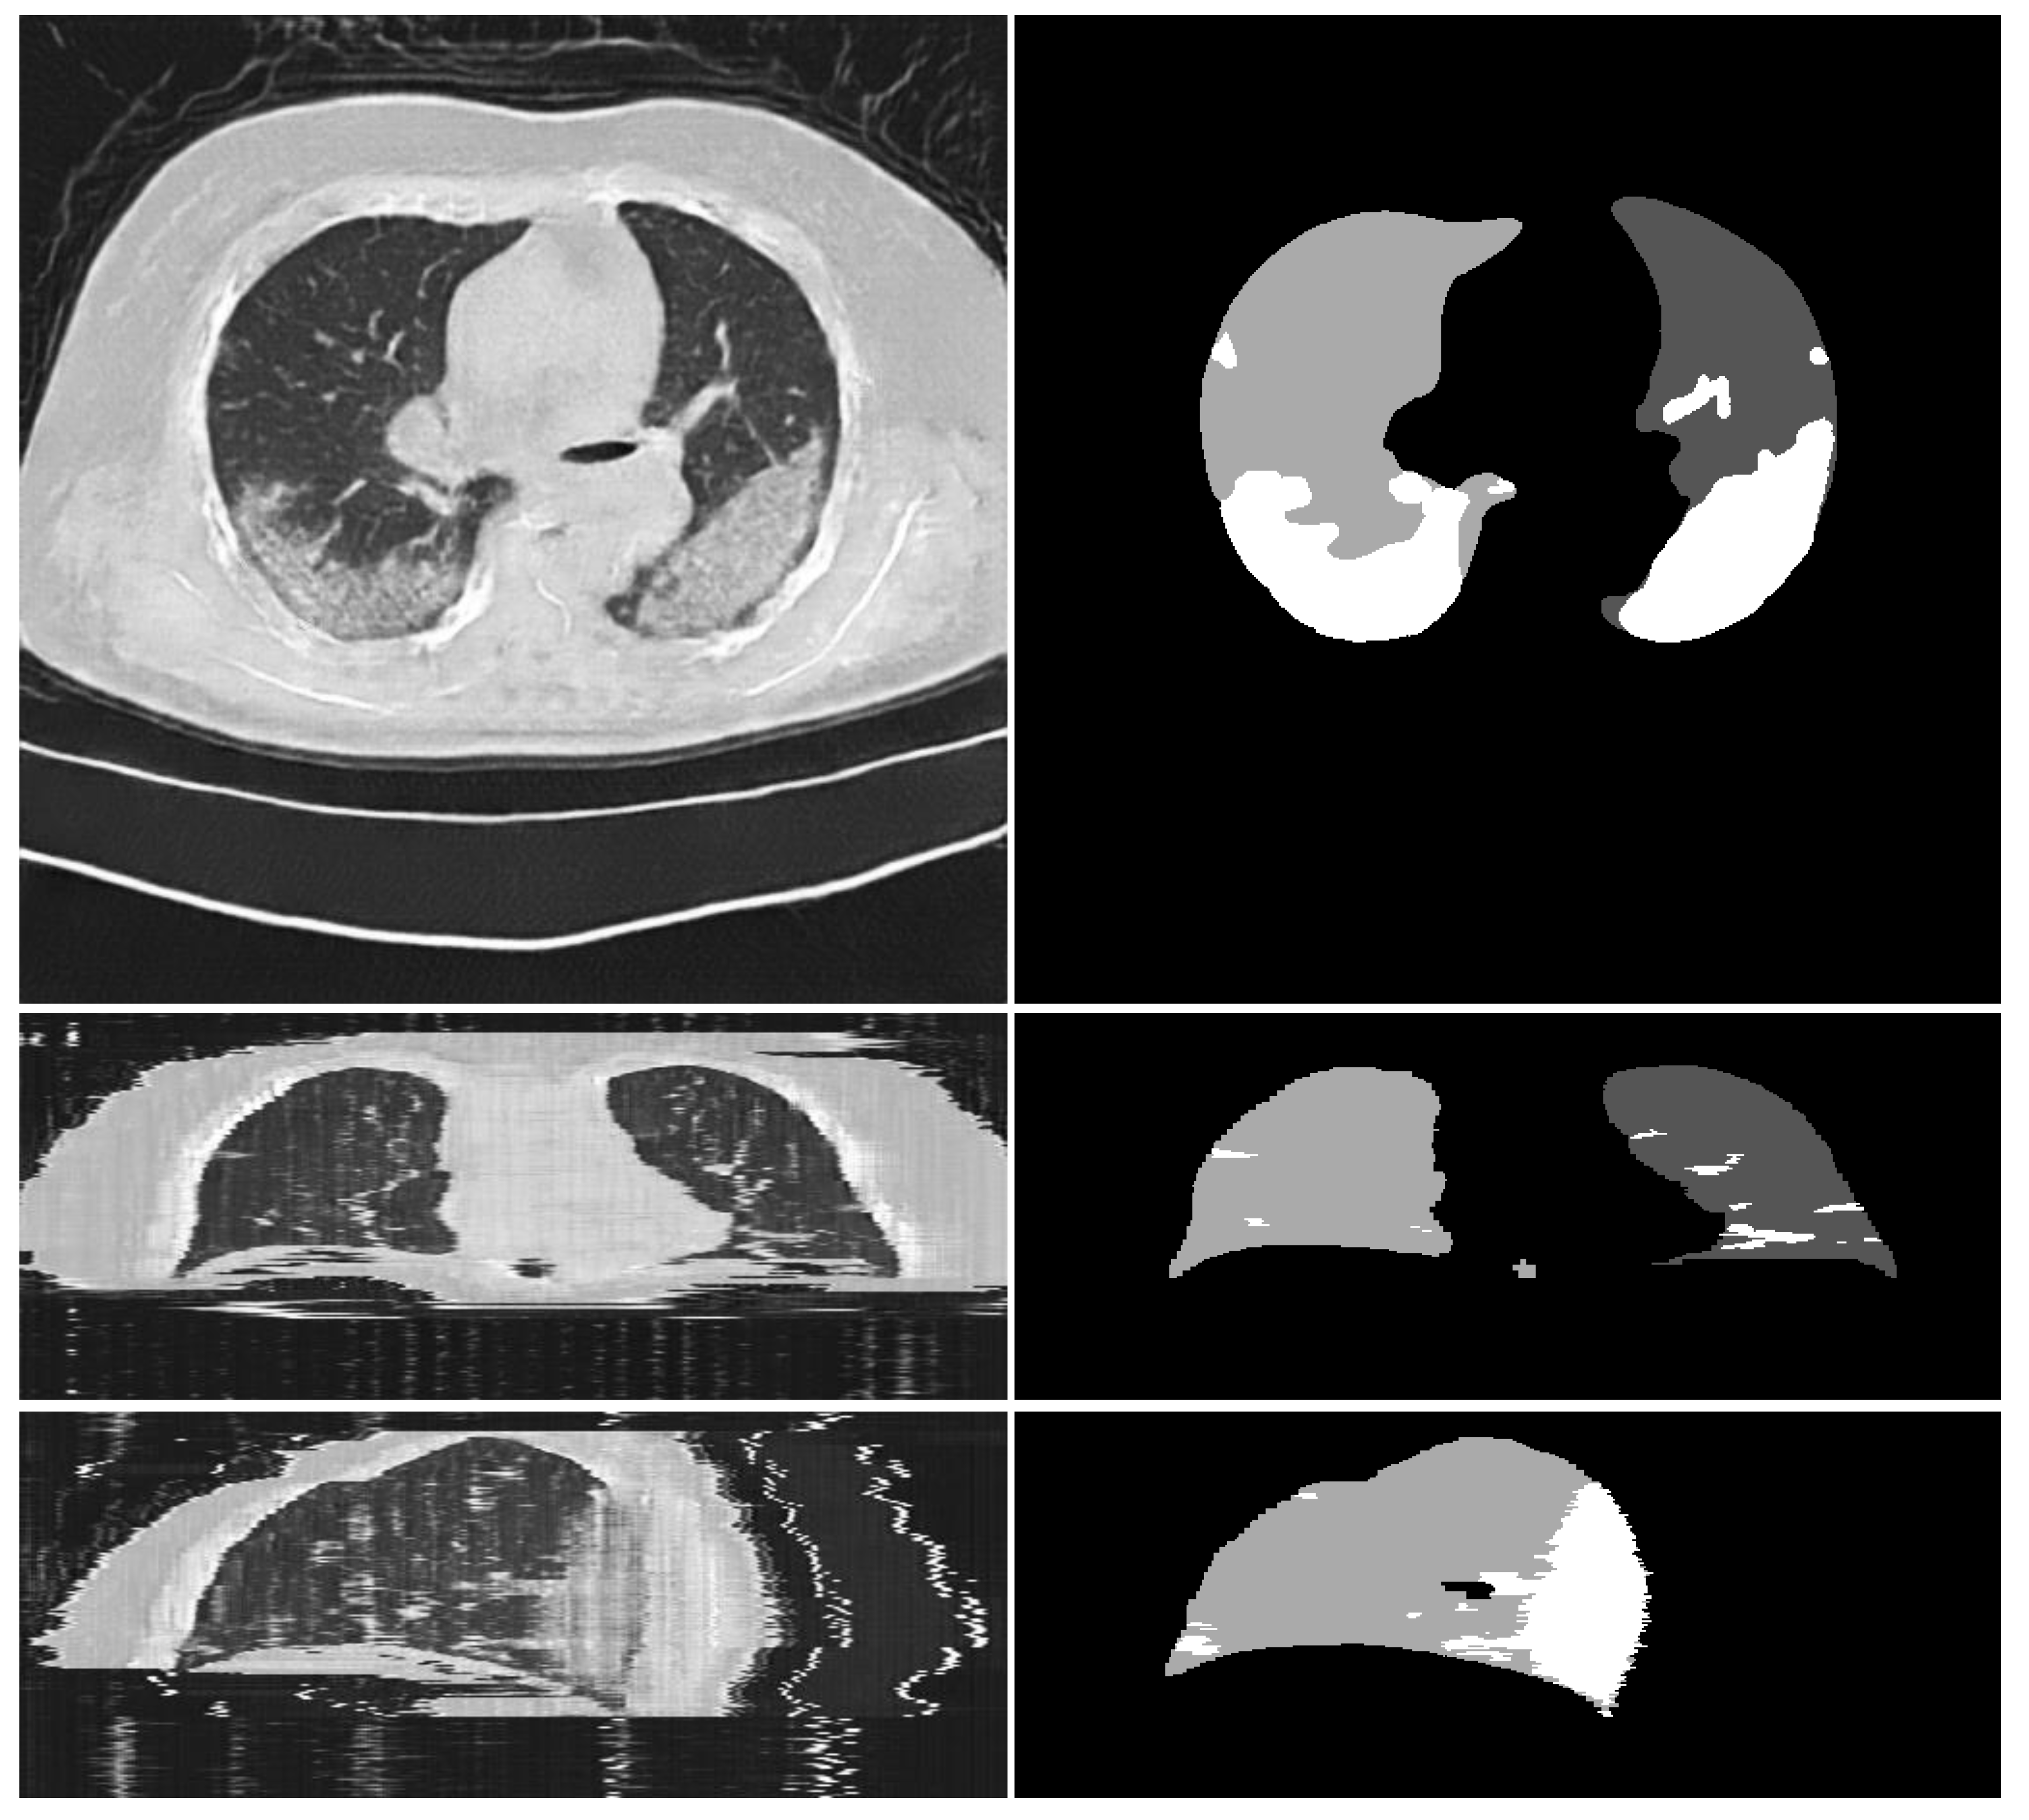

3.1. Experiments on Synthesizing Radiological Images

3.1.2. Ablation Experiments